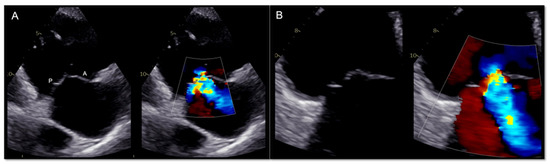

4.1. Two-Dimensional and Three-Dimensional Transthoracic and Transesophageal Echocardiography

- Carpenito, M.; Cammalleri, V.; Vitez, L.; De Filippis, A.; Nobile, E.; Bono, M.C.; Mega, S.; Bunc, M.; Grigioni, F.; Ussia, G.P. Edge-to-Edge Repair for Tricuspid Valve Regurgitation. Preliminary Echo-Data and Clinical Implications from the Tricuspid Regurgitation IMAging (TRIMA) Study. J. Clin. Med. 2022, 11, 5609. [Google Scholar] [CrossRef]

- Coisne, A.; Scotti, A.; Taramasso, M.; Granada, J.F.; Ludwig, S.; Rodés-Cabau, J.; Lurz, P.; Hausleiter, J.; Fam, N.; Kodali, S.K.; et al. Prognostic Value of Tricuspid Valve Gradient after Transcatheter Edge-to-Edge Repair. JACC Cardiovasc. Interv. 2023, 16, 706–717. [Google Scholar] [CrossRef]

- Montalto, C.; Sticchi, A.; Crimi, G.; Laricchia, A.; Khokhar, A.; Giannini, F.; Ferlini, M.; Colombo, A.; Latib, A.; Mangieri, A. Functional and Echocardiographic Improvement after Transcatheter Repair for Tricuspid Regurgitation: A Systematic Review and Pooled Analysis. JACC Cardiovasc. Interv. 2020, 13, 2719–2729. [Google Scholar] [CrossRef]